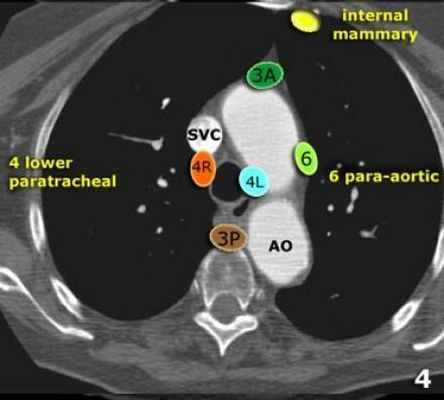

В этой статье представлены иллюстрации и КТ-изображения для лучшего понимания этой классификации.

3А Преваскулярные лимфатические узлы не примыкают к трахее как узлы 2 группы, а располагаются кпереди от сосудов (от задней стенки грудины, до передней стенки верхней полой вены справа и передней стенки левой сонной артерии слева)

3P Превертебральные(Ретротрахеальные) располагаются в заднем средостении, не примыкают к трахее как узлы 2 группы, а локализуются кзади от пищевода.

4R Нижние паратрахеальные от пересечения нижнего края плечеголовной вены с трахеей до нижней границы непарной вены, вдоль правой стенки трахеи до ее левой стенки.

4L Нижние паратрахеальные от верхнего края дуги аорты до верхнего края левой главной легочной артерии

6. Парааортальные лимфатические узлы лежат спереди и сбоку от восходящей части дуги аорты

На изображении слева 3А узел в преваскулярном пространстве. Обратите внимание так же на ниже расположенные паратрахеальные узлы справа относящиеся к 4R группе.

На изображении слева мы видим 4R паратрахеальные узлы. Кроме того здесь представлен узел кнаружи от дуги аорты, то есть 6 группы.

Группы лимфатических узлов на аксиальных компьютерных томограммах

3. Преваскулярные и ретротрахеальные: кпереди от сосудов (3А) и превертебральные (3Р)

4. Нижние паратрахеальные: ниже верхнего края дуги аорты до уровня главного бронха

6. Парааортальные: узлы лежащие кпереди и кнаружи от восходящего отдела аорты и дуги аорты под верхним краем дуги аорты.